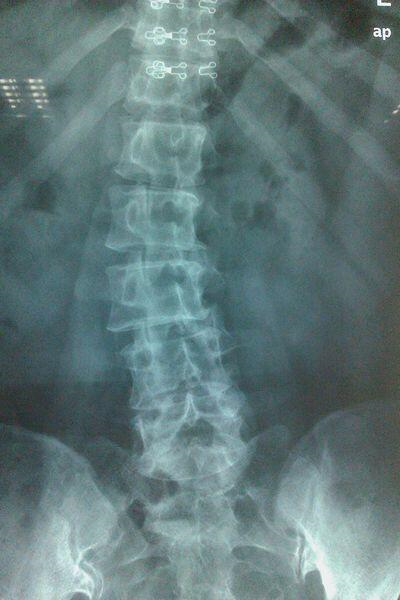

您患过腰痛吗?您都是在什么情况下出现腰痛呢?以我的诊疗经验来说,即使是在大街上随机抽样问这两个问题,我相信大多数人的回答都会是肯定的。因为腰疼这个病症的确极其常见,尤其是40岁以上的中老年人。给大家看个X光片,就知道我们的腰如果不注意保护和锻炼会是什么样子了:

image.png